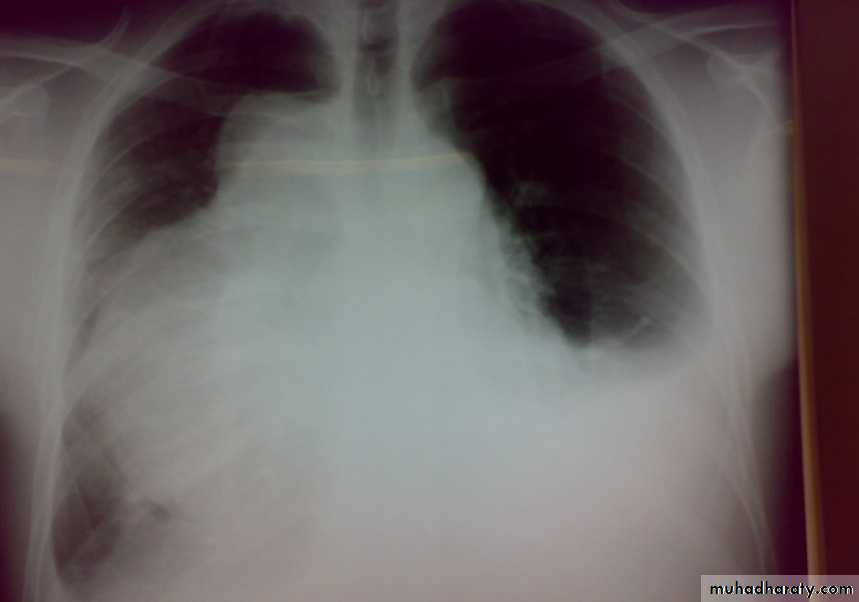

• 4-Pleural effusion

• Is the accumulation of fluid in the pleural space excessive transudation or exudation of the interstitial fluid from the pleural surface. It is signify pleural or systemic disease .

• Its effect depends on its size (mild , moderate or massive ) & the state of the underlying lung .It is classified as transudate when the protein content is less than 3g% or exudates when protein content is more than 3 gm % .Clinically patients will present with dyspnea & pleuritic chest pain

• Radio logically (concave meniscus sign)